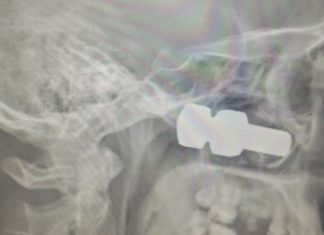

З-під колеса вантажівки вилетів болт, який потрапив в голову.

Якщо ви дивилися фільм «Пункт призначення», то після прочитання цього поста вам стане ще страшніше виходити на вулицю. Житель Лесосибирска чекав на трасі свого...